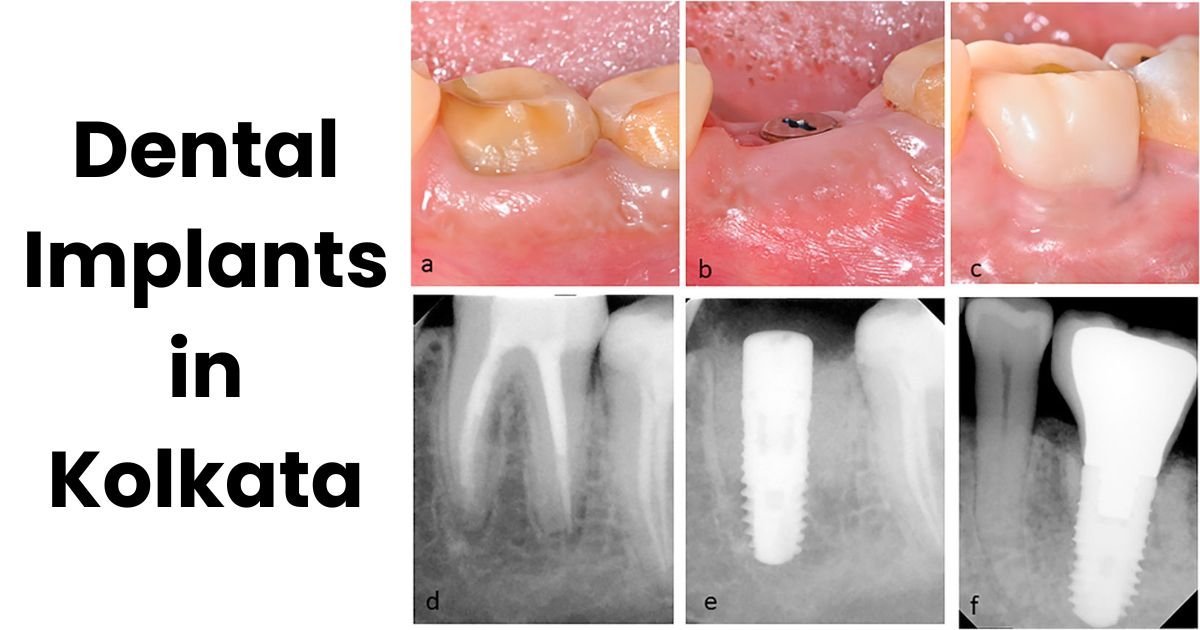

Restore Your Smile with Dental Implants in Kolkata

• May 20, 2025

• Comments: 0